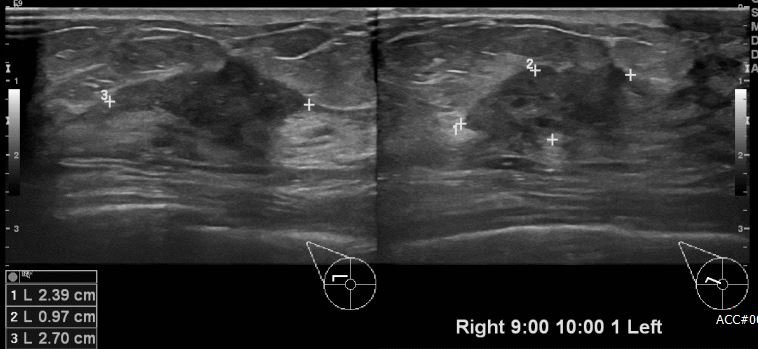

상기환자 우측 만져지는 멍울로 내원하신 50대 여성분으로 유방 초음파상 우측 9시~10시

방향에서 1cm 떨어진 거리의 의심스러운 멍울 조직검사 시행하여 우측 침윤성 유관암

진단 되었습니다.